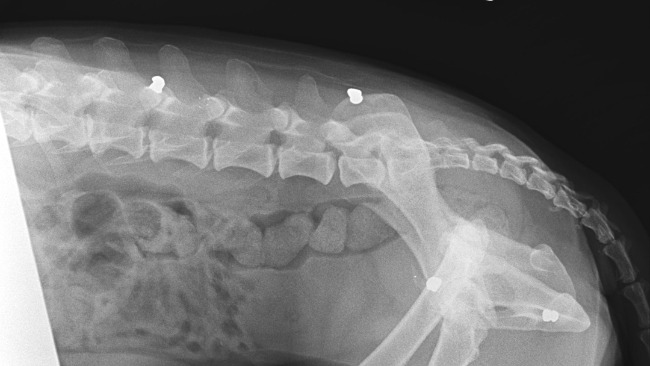

Ostatnie wizyty u specjalistów kompletnie mnie rozwaliły. U ortopedy prześwietlenia wykazały silne zmiany zwyrodnieniowe prawie wszystkich stawów, w tym te niezwykłe bolesne w bioderkach oraz zwichnięcie rzepki. Dlatego Jogi ma takie problemy z chodzeniem.

Ale na zdjęciach zobaczyłam coś znacznie gorszego, co rozwaliło mi serce na miliony kawałków. Ten biedak jest cały nafaszerowany śrutem. Jakiś zwyrodnialec strzelał do niewidomego psiaka, który nie wiedział, z której strony padały strzały i nawet nie był w stanie uciekać. CZY MOŻECIE WYOBRAZIĆ SOBIE TEN STRACH I CIERPIENIE ???!!!!!!!!!!!!!!!!!!!!! Jakim trzeba być zwyrolem i zarazem tchórzem, żeby strzelać do kalekiego, niewidomego zwierzaka.